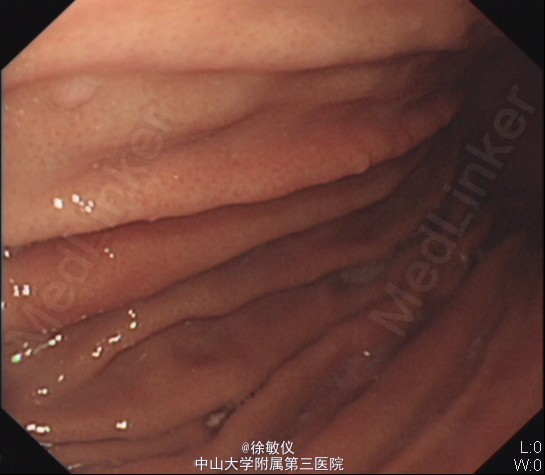

行胃镜检查,示1、胃多发息肉, 2.慢性浅表糜烂性胃窦炎。予行息肉钳除术。病理:(胃底、胃体息肉)胃底腺息肉。 予切除息肉后,予护胃调节植物神经功能等治疗,腹痛症状渐好转。